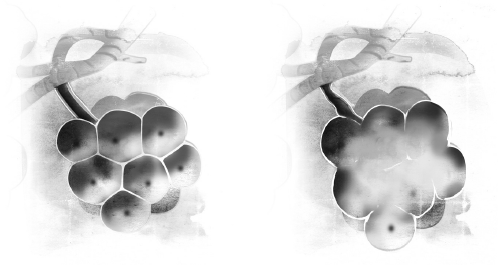

肺脏是两个具有弹性的容器,可以容纳四公升到六公升的空气,视体型大小而定。它是弹性极大、类似海绵的组织,而且里面总是含有一些空气。

由于肺脏具有超强的弹性,因此它的形状是由肋骨的结构和横膈膜的活动来决定。横膈膜和肋骨发生活动时,肺脏自然也随之改变形状。许多人不清楚肺脏的大小和位置,也不知道肺脏里面永远会留下一些空气,它从来就不会消气消到完全扁掉。

肺脏位于胸廓里面、横膈膜的上方,一片肺在左边,另一片在右边,两片肺的形状并非左右对称。事实上,人的右肺有三叶,而且比左肺稍微大一些些。左肺只有两叶,而且稍微小一点,因为它必须跟心脏共用胸腔的空间。

人体的肺脏是立体的锥形结构,肺脏下方跟横膈膜相邻。肺脏的顶部呈圆形,当它完全膨胀时,锁骨上方到接近胸廓底部的空间会被它填满,而且肺脏背面的组织比正面的组织还多。肺脏包覆在一层薄薄的组织膜里面,称为胸膜,这种组织膜同样也存在于胸腔内部。有一层薄薄的液体,发挥润滑剂的作用,让肺脏可以顺畅地活动,随着一呼一吸的动作而膨胀起来、消扁下去。

✘误解一:肺脏是个小小的器官,位于身体的中央

许多人对于肺脏的大小和位置缺乏正确的感知,他们所想的跟事实差距相当远。成人的肺脏大小变化很大,视性别、身高和姿势而定。

多数人身上的肺脏长度介于二十五至三十五公分之间,最宽的地方大约有十至十五公分。肺脏的形状像是切掉顶部的椭圆形,类似橄榄球的形状,不过比橄榄球小一些、窄一些,重量一般是○.九至一.四公斤重。

在左页的X光片中,你可以看到两侧肺脏的实际大小和位置。你所画的图跟这张X光片比起来,有没有什么不同呢?

肺脏的顶部延伸到锁骨上方,当你吸气吸到饱的时候,肺脏的底部几乎会延伸到肋骨的下缘。